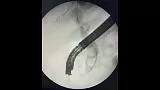

Рентгенологическая картина расширенния желчных протоков и наличие конкрментов в холедохе. Произведена эндоскопическая ограниченная папиллосфинктеротомия, отмечалось поступление темной желчи. Ревизия корзиной Дормия дали основания полагать ,что конкременты плотной консистенции.

Учитывая состояние пациента, большой степени вероятности осложнений и наличие крупных конкрементов в холедохе , принято решение следовать общепринятой тактике лечения при юкстапапиллярном расположении БДС - воздержаться от одноэтапного проведения операции с литэкстракцией. Произведено стентирование холедоха пластиковым стентом типа Pig-tail 10 Fr-130 мм, чем достигнуто адекватное дренирование желчных путей. Послеоперационный период протекал без осложнений. Биохимический анализ крови: билирубин общий-17.0 , билирубин прямой -13.0 , билирубин непрямой - 4, с-реактивный белок -24.3, скорость клубочковой фильтрации-37,4. По представленным результатам обследования в послеоперационом периоде, можно отметить положительную динамику в показателях пигментного обмена. Пациент в удовлетворительном состоянии выписан на амбулаторное лечение .